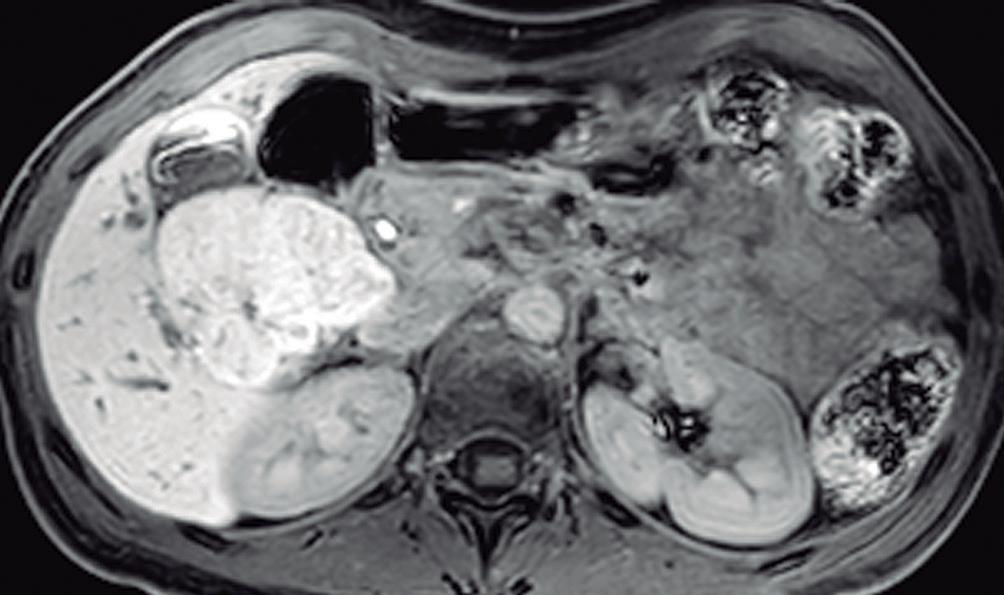

En la RM los hemangiomas son lesiones con señal hipointensa en T1 e hiperintensa muy marcada en T2. Esta última característica los diferencia de otras lesiones benignas o malignas, con excepción de los quistes, que presentan señal más elevada debido a su contenido acuoso.1 El patrón de realce poscontraste es igual al que muestra la TC. (Figura 2) En la secuencia de difusión no presentan un patrón restrictivo, si bien pueden exhibir una señal brillante en valores b altos (parámetro que pondera la difusión); esto se debe al efecto brillo T2 y no a la restricción verdadera, por lo que el mapa del coeficiente de difusión aparente (ADC, por sus siglas en in-

A: T1 post contraste en fase venosa portal; B, y fase de equilibrio; C: Muestran lesiones en segmentos IV y VI con una señal marcadamente hiperintensa en la secuencia T2 y

Lesiones benignas localizadas en el hígado desde la mirada de las imágenes Mariano Volpacchio Figura 1. Hemangioma en tomografía computada. Imágenes axiales de la TC sin contraste Figura 2. Hemangioma en la RM. Imágenes axiales de la RM en secuencia T2 con supresión grasa con el refuerzo similar a las estructuras vasculares de aspecto globular y progresivo en sucesivas fases. Nótese la heterogeneidad del hemangioma de mayor tamaño en segmento VI. A B C